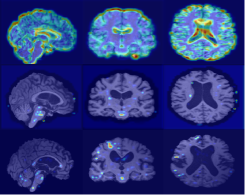

Refer to caption

(a) Original sMRI

(b) MixStyle

(c) EM1

(d) EM2

AIBL

(e) Original sMRI

(f) MixStyle

(g) EM1

(h) EM2

OASIS

(i) Original sMRI

(j) MixStyle

(k) EM1

(l) EM2

Figure 3: Grad-CAM visualizations on 3D sMRI samples across cohorts. The figure presents NC, MCI and AD subjects from ADNI (top row), AIBL (middle row), and OASIS (bottom row). For each cohort, columns show: original sMRI scans, MixStyle baseline, EM1 based on mean, standard deviation, and skewness, and EM2 extending EM1 with kurtosis.

Grad-CAM visualizations in Fig. 3 show that, compared to MixStyle, the proposed EM variants produce more stable and focused activations within cortical and subcortical regions commonly affected by AD. EM1 provides the clearest localization, reducing noisy responses outside brain tissue and highlighting disease-relevant areas more consistently. EM2 shows a similar trend, though its attention maps are slightly more diffuse. These improvements are most evident in ADNI and AIBL, while OASIS shows smaller but consistent gains. Overall, incorporating higher-order moments encourages the model to focus on more anatomically meaningful structures.